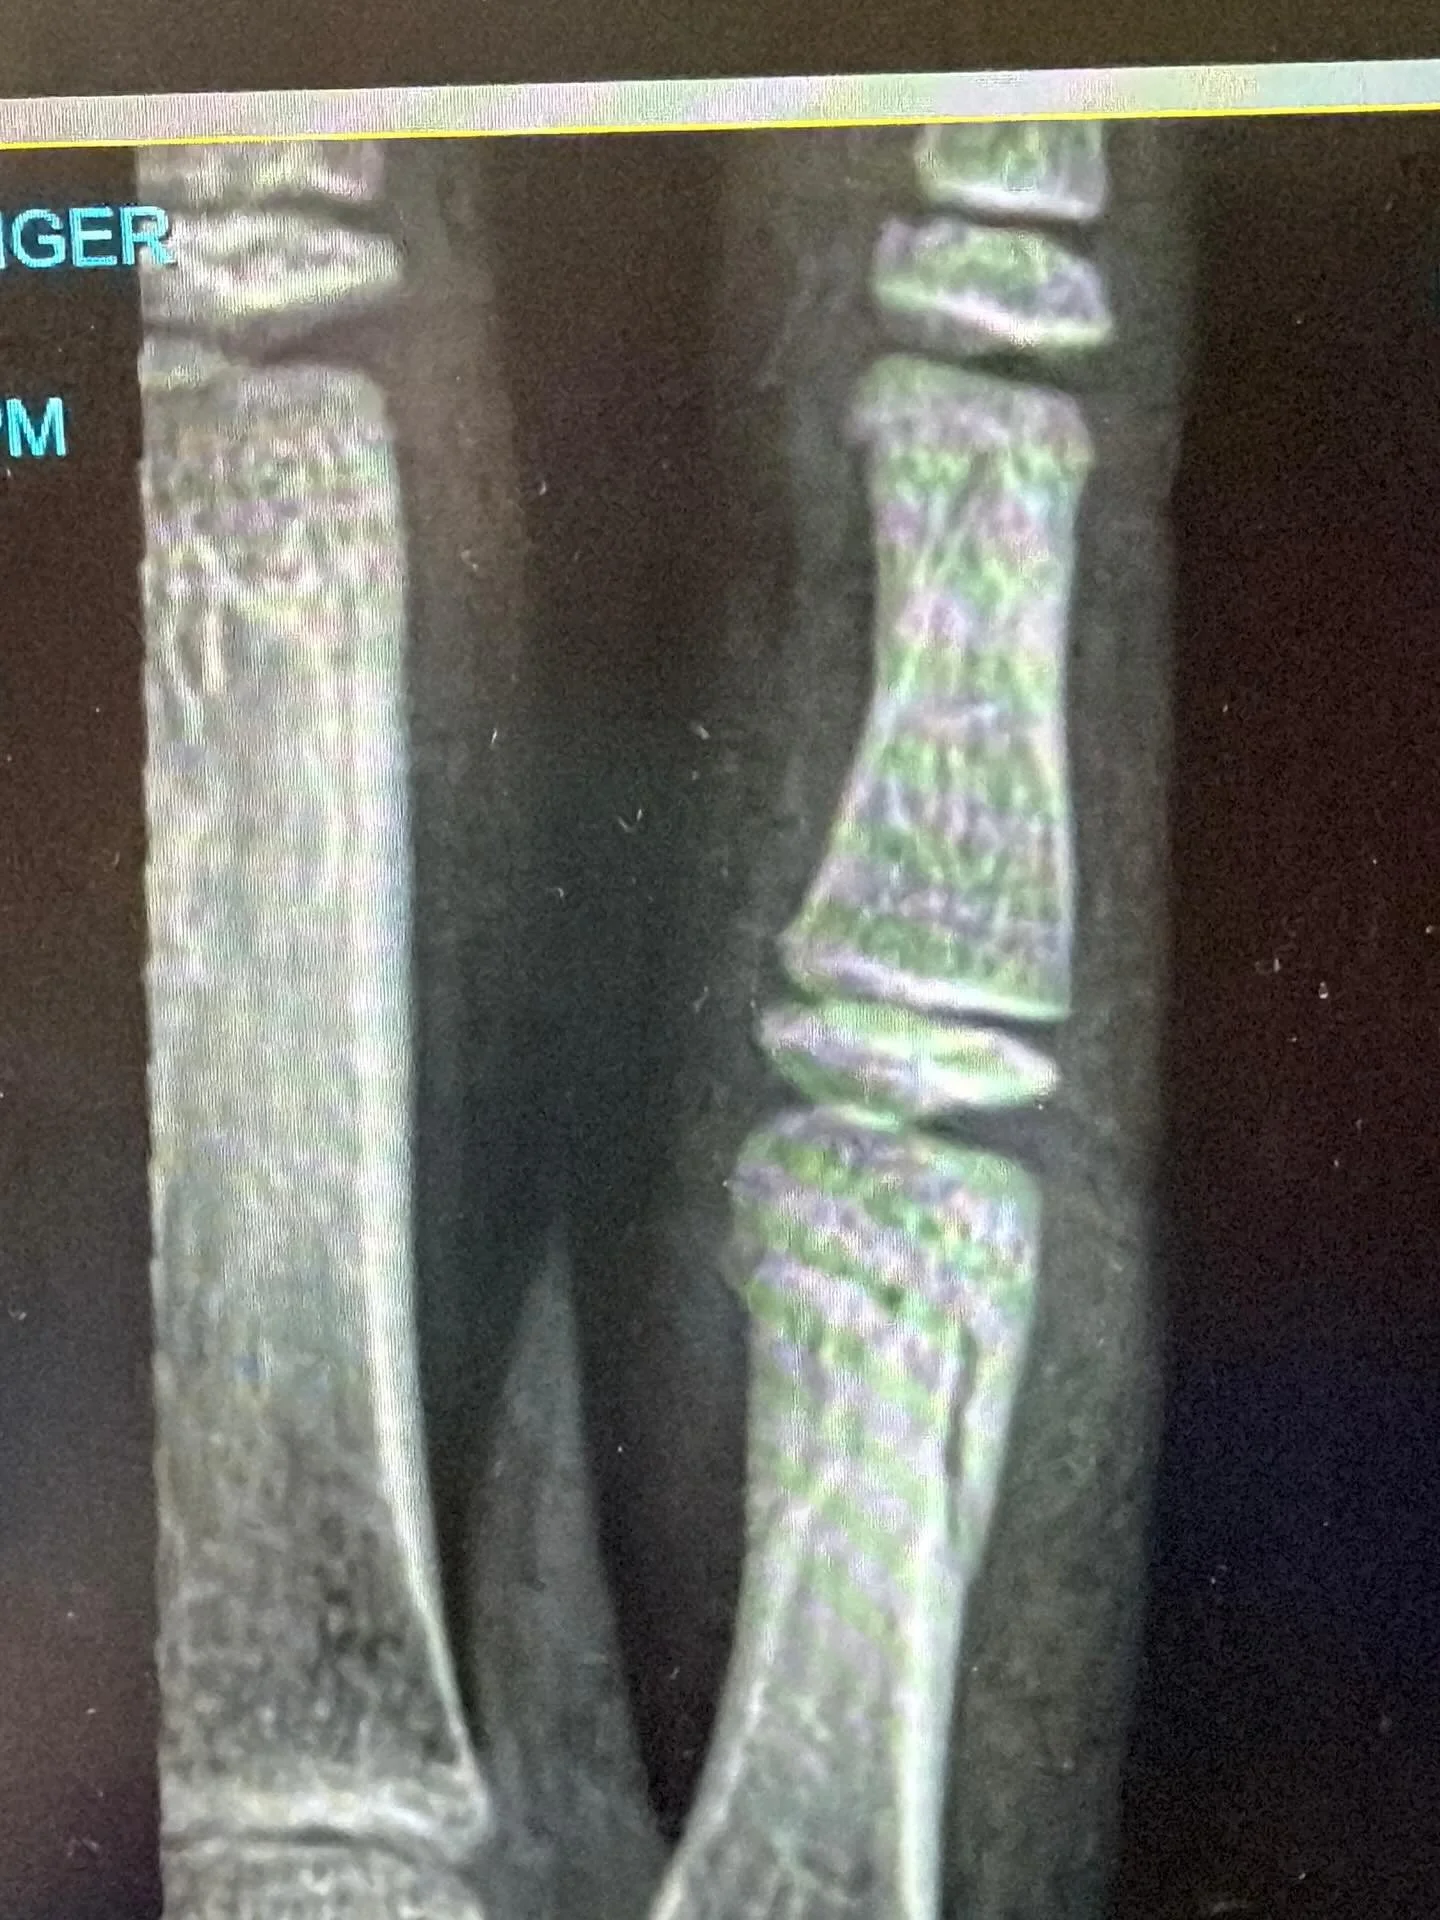

Hand therapy is a specialised form of therapy that focuses on treating injuries and conditions of the hand and upper limb. Our expert team has undergone extensive training in hand therapy and possesses the knowledge and skills to assist with the rehabilitation of various hand-related issues, including injuries, diseases and congenital conditions affecting the hand, wrist, forearm or elbow.

At The Hand Therapy Group, we recognise that each patient and injury is unique. Therefore, we develop personalised treatment plans tailored to address your specific needs and goals. Whether you recently underwent surgery, sustained a sports-related injury, experienced an accident at work or during recreational activities or are dealing with arthritis or other degenerative conditions, our advanced and gentle techniques, along with customised exercises, will help you regain your quality of life.

The Hand Therapy Group is proud to offer a comprehensive range of specialised hand therapy services in Auckland and Whakatane. Our dedicated team of Physiotherapists and Occupational Therapists provides expert care and rehabilitation for a wide range of hand and upper limb injuries and conditions. Whether you're dealing with fractures, sprains, dislocations, nerve injuries, tendonitis, arthritis or post-surgical rehabilitation, each hand therapist in our Auckland and Whakatane clinics have the knowledge and expertise to help you on your path to recovery. Through a combination of manual therapy techniques, therapeutic exercises, custom splinting and patient education, we strive to optimise your hand function and enhance your overall wellbeing.